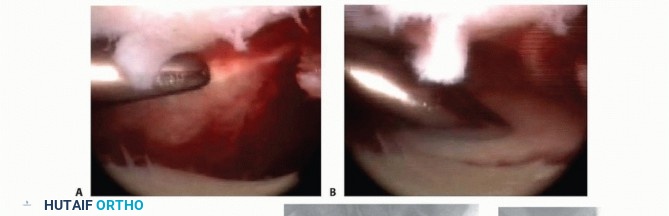

### TECH FIG 4 • A. A standard volar approach is made, centered over the flexor carpi radialis tendon, and the fracture site is exposed. B. A volar distal radius locking plate is applied. The initial screw is placed through the proximal plate to secure the plate to the shaft. C. The intra-articular reduction is viewed under fluoroscopy and provisionally pinned. A displaced intra-articular fracture fragment can still be identified. D. The arthroscope is in the 3-4 portal, showing the volar capsule blocking reduction of the radial styloid fragment. E. Joysticks previously inserted into the radial styloid fragment are then used to control and anatomically reduce the radial styloid fragment. F. The arthroscope is in the 6R portal looking across the wrist. Anatomic reduction of the radial styloid fragment is documented. G. Once the anatomic restoration of the articular surface is evaluated both arthroscopically and fluoroscopically, the distal screws are placed in the plate. H. Fluoroscopic view showing anatomic restoration to the articular surface of the distal radius. I. The patient had an associated osteochondral fracture of the lunate, not visible on plain radiographs. The displaced fragment is arthroscopically removed.

Apply a volar distal radius locking plate to stabilize the volar bone fragments ( TECH FIG 4B). Place a screw in the proximal portion of the plate first to reduce the plate to the shaft. Provisionally pin the distal fragments through the plate. Manipulate the articular fragments under fluoroscopy to obtain as anatomic a reduction as possible ( TECH FIG 4C,D). Suspend the wrist in the traction tower and reduce the articular fragments arthroscopically ( TECH FIG 4E,F). If articular reduction is not anatomic, remove the pins and fine-tune the reduction. Once the fracture reduction is thought to be anatomic, place the distal screws through the plate ( TECH FIG 4G-I). It is important that the fracture be reduced to the plate, with no gap between the plate and the bone. This can be achieved by flexion of the wrist in the tower and by insertion of a nonlocking screw first, before the insertion of standard locking screws. Place the remaining proximal and distal screws if the reduction is anatomic under both fluoroscopy and arthroscopy. 1. ### Reduction and Stabilization of a Dorsal Die-Punch Fragment It is not possible to see the reduction of a dorsal die-punch fragment through the volar approach when stabilized with a plate. Arthroscopy can be helpful in this scenario. Insert the volar plate as previously described and provisionally fix the device to the radius. Frequently, the dorsal fragment may still be slightly proximal in relation to the radial shaft. The dorsal die-punch fragment is best seen with the arthroscope in the 6R portal. Establish the volar radial portal between the radioscaphocapitate ligament and the long radiolunate ligament, as viewed directly through the previous performed volar approach. 23 Percutaneously elevate and anatomically reduce the dorsal diepunch fragment as viewed arthroscopically. Once this has been achieved, place the screws into the plate and observe their path arthroscopically to ensure adequate stabilization of the dorsal die-punch fragment. 2. ## Ulnar Styloid Fractures Following anatomic reduction of the distal radius fracture, insert the arthroscope in the dorsal 3-4 portal and the probe in the 6R portal. Palpate the tension of the articular disc. Good tension indicates that the majority of the peripheral TFCC fibers are intact or still attached to the proximal ulna. A peripheral tear of the articular disc is repaired arthroscopically when detected. 30 Stabilization of a large ulnar styloid fragment is considered when the articular disc is lax by palpation and no peripheral TFCC tear is identified ( TECH FIG 5). In this instance, the majority of the fibers of the TFCC are attached to the displaced ulnar styloid fragment. Make a small incision between the extensor carpi ulnaris and the flexor carpi ulnaris tendons and identify the fracture site. Retrieve the distal fragment, which often displaces in a distal and radial direction. Mobilize the styloid fragment using a no. 15 blade, taking care to protect the TFCC insertion. Reduce the fragment anatomically, under direct visualization, and insert a guidewire in a retrograde manner for provisional stability. Stabilize the ulnar styloid fragment using either a tension band technique (with wire and two K-wires) or, preferably, using a micro headless cannulated screw. Place the cannulated headless screw over the guidewire and verify fracture reduction with fluoroscopy. Insert the arthroscope into the 3-4 portal and the probe into the 6R portal to document restoration of TFCC tension.

TECH FIG 5 • In this case, following reduction to the distal radius fracture, the articular disc was palpated and found to be lax but with no peripheral tear. The large ulnar styloid fragment was reduced with a micro Acutrak screw.*